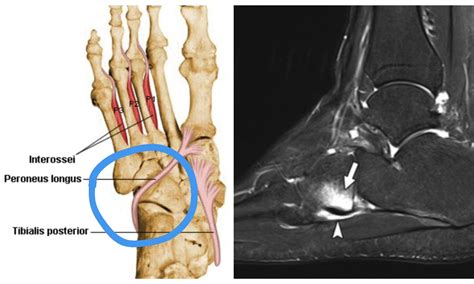

To grasp the significance of a Peroneus Longus Tendon Tear, it is helpful to understand the function of the peroneal tendons. There are two primary peroneal tendons—the peroneus longus and the peroneus brevis. They run side-by-side along the lateral (outer) aspect of the ankle. Their primary roles include:

• Support: The peroneus longus tendon specifically passes under the foot, helping to maintain the arch and support the first metatarsal.

• MRI (Magnetic Resonance Imaging): This is the gold standard for visualizing soft tissue. It provides high-resolution images that clearly show tears, inflammation, or degeneration within the tendon.